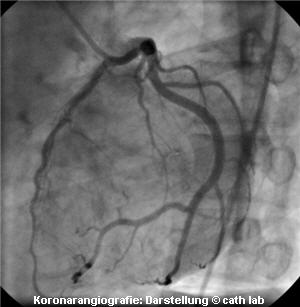

Herzkatheterlabor,Mediziner,Ärzte,Primare,Privatordination,gesetz,behandlung,ärzte,station,gkk,operation,termin,gesund Herzkatheter-Untersuchungen unterschieden sich ganz wesentlich von anderen Operationen: man ist bei Bewusstsein und kann mit dem behandelnden Arzt sprechen. So bin ich im OP während der Behandlung mit dem Primar auf meine Befunde aus Wels zu sprechen gekommen. Erst dann hat er sie angefordert und gelesen und anschließend weitergemacht. Der (unauffindbare) Befund der Cardio-CT wurde gar nicht benötigt.

kroronarangiografie,bei bewusstsein,Mediziner,Ärzte,Primare,Privatordination, praktische ärzte,befund,fachärzte,berufung,medizinischEinen Tag nach der Behandlung durfte ich wieder heim. Ein paar Tage später kamen übrigens in einem Kuvert ohne Begleitschreiben die angeblich nicht auffindbaren Unterlagen mit der Diagnose des Cardio-CT und den Zugangsdaten zurück.